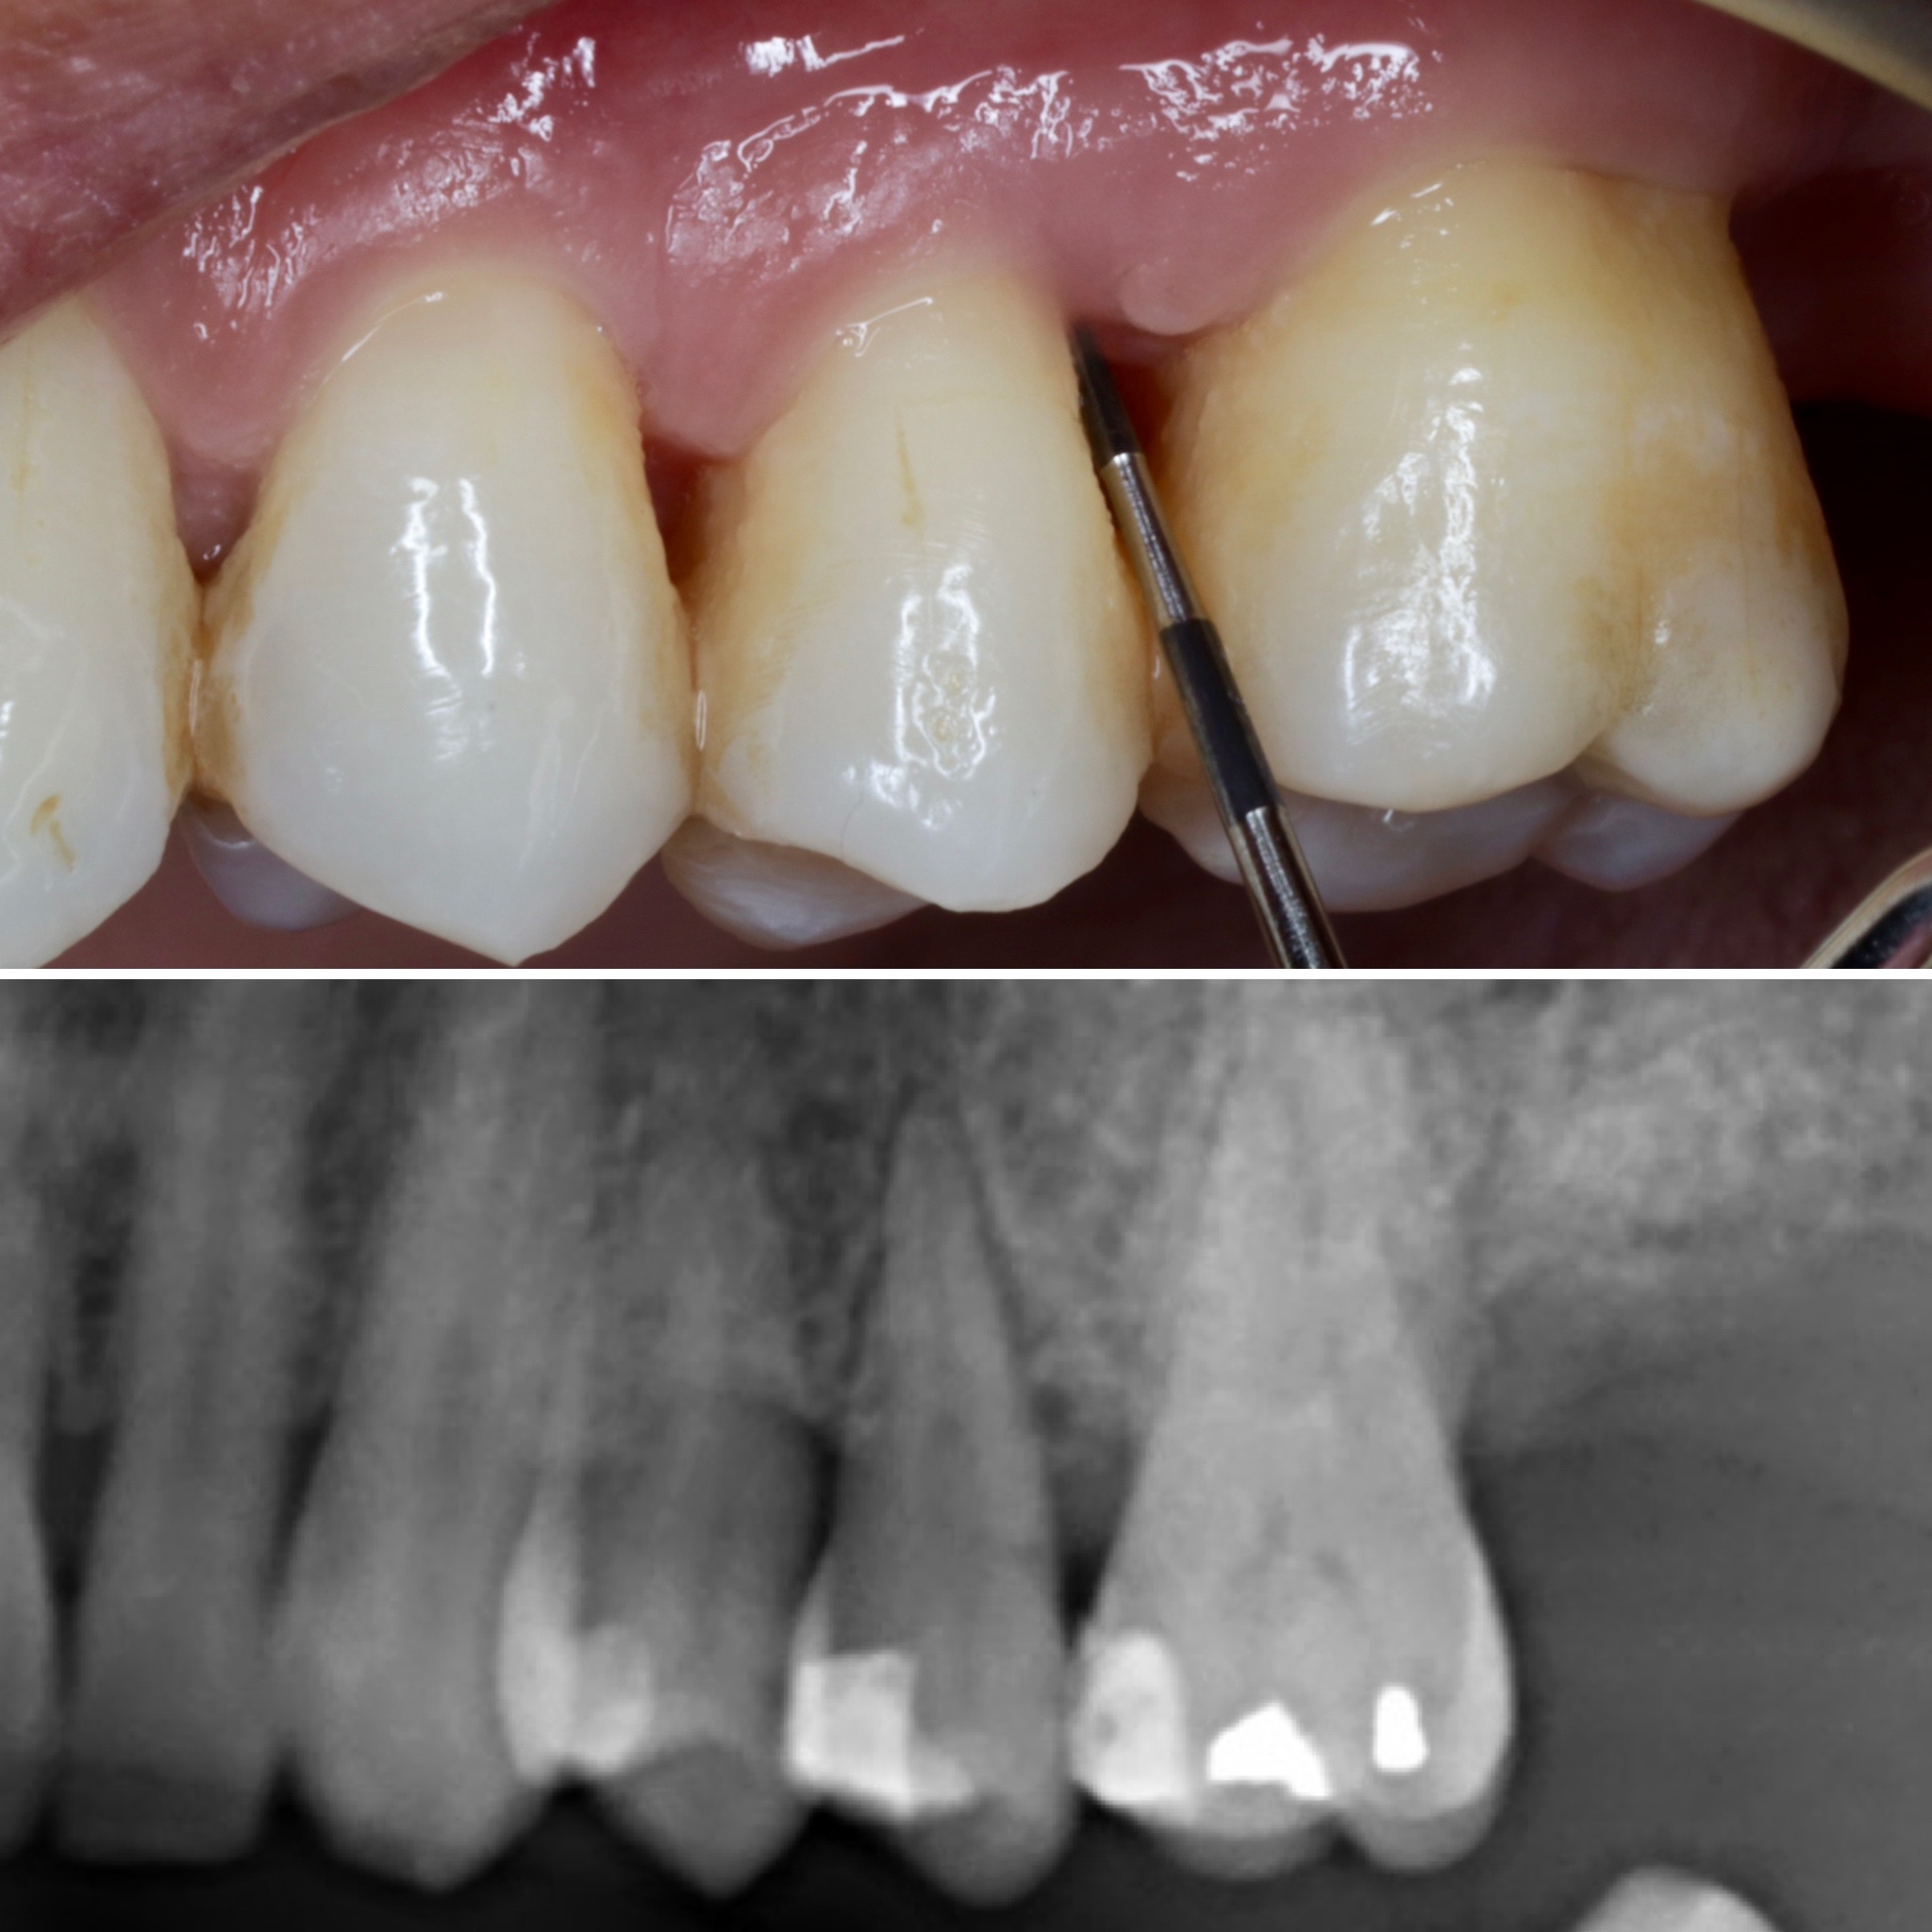

Se presenta un caso clínico de restauración directa en resina composite, ejemplo del valor de la precisión y la técnica meticulosa incluso en procedimientos considerados rutinarios dentro de la práctica diaria. El caso pone en evidencia la importancia del control de la morfología, la textura y la integración cromática, así como del adecuado aislamiento del campo operatorio y la estratificación del material, factores determinantes para conseguir un resultado natural, funcional y duradero. A través de una ejecución cuidadosa, se logró una restauración estéticamente imperceptible y funcionalmente estable, que respeta los principios de mínima invasión y adhesión efectiva. Este tipo de procedimientos, aunque cotidianos, reflejan la constancia y el nivel de exigencia clínica necesarios para ofrecer odontología de calidad en todos los casos, independientemente de su complejidad.